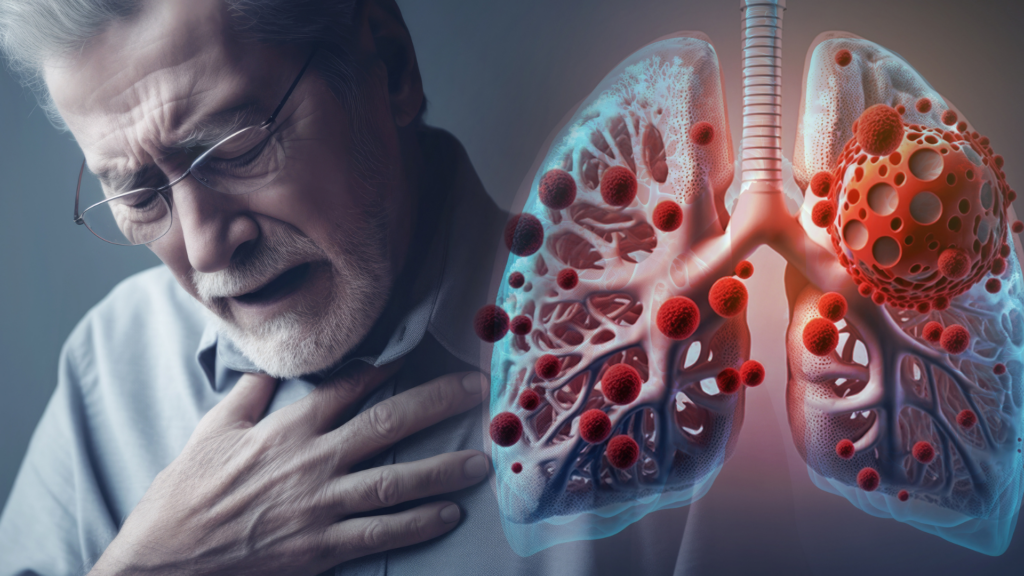

Supervivencia a cáncer de pulmón sube de 23 al 60 % con diagnóstico temprano, dice experta

Datos del programa SEER en Estados Unidos muestran que la supervivencia a cinco años alcanza el 62.8 % cuando el tumor se diagnostica en fase localizada, cae al 34,8 % en casos regionales y desciende al 8 % en los metastásicos.